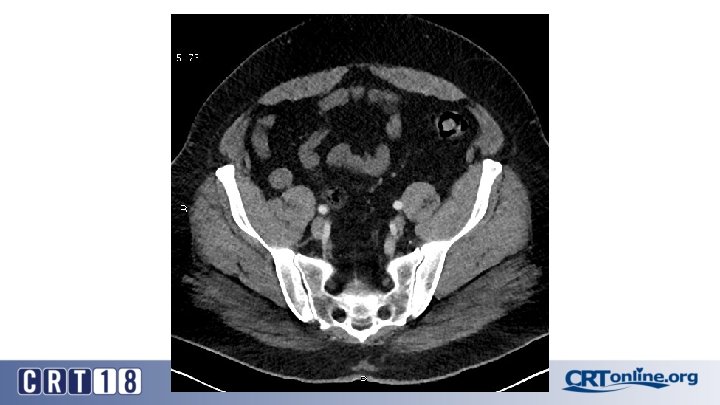

Blue Toe Syndrome

Returns Next day

Failed recanalization: BKA